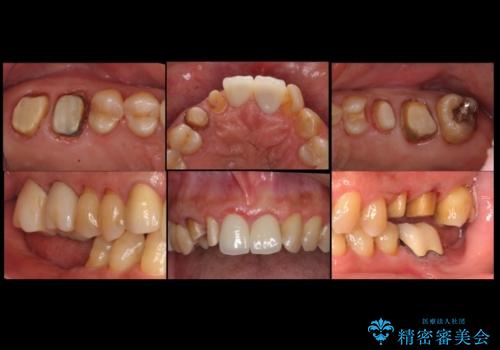

また、向かい合う上の歯が挺出(伸び出してしまうこと)しており、インプラントを入れることが難しかったため、長さを短くかぶせ治しました。

また、上顎前歯以外の根の治療のやり直しを行いました。

上顎前歯は他院で根管治療とセラミックを行なったとのことで、歯肉縁下形成のため、歯肉の腫れが治りにくい状況でしたがやり直しは希望されませんでした。

セラミックが欠けるのを防ぐため、また、左上7は対合歯がなく挺出してしまうのを防ぐため、ナイトガードを就寝時に装着していただいています。